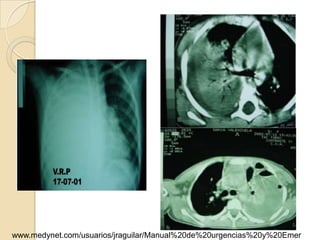

Rx. Tórax PA. (A). posterior a la                 Rx. Tórax PA.(B). Disminución de los      Rx. Tórax PA.(C). Aumento

insercion del tubo de tórax para                  espacios intercostales izquierdos,        compensatorio del volumen

drenaje pleural. radiopacidad difusa              engrosamiento pleural severo ,            pulmonar derecho, mayor

del hemitórax izquierdo, con colapso              borramiento de los senos costo-           aclaramiento del vértice y

parcial pulmonar, desviación                      frénicos, elevación hemi-diafragma        disminución de espacios

mediastinal hacia la derecha. Por                 izquierdo.escoliosis dorsal leve y poco   intercostales del hemitórax izquierdo.

proceso neumonico con derrame                     aclaramiento del vertice porfibrosis      retracción del diafragma izquierdo,

pleural.                                          pleural y atelectasia pulmonar.           escoliosis marcada por fibrotorax

Cortes tomograficos A - B - C - D : Desde carina hacia base del

tórax, dezplazamiento de la carina a la derecha, severo

engrosamiento pleural izquierdo, con tabicamiento, disminucion del

volumen del hemitorax izquierdo, además reporta areas de atelectasia

pulmonar en lóbulo inferior izquierdo.